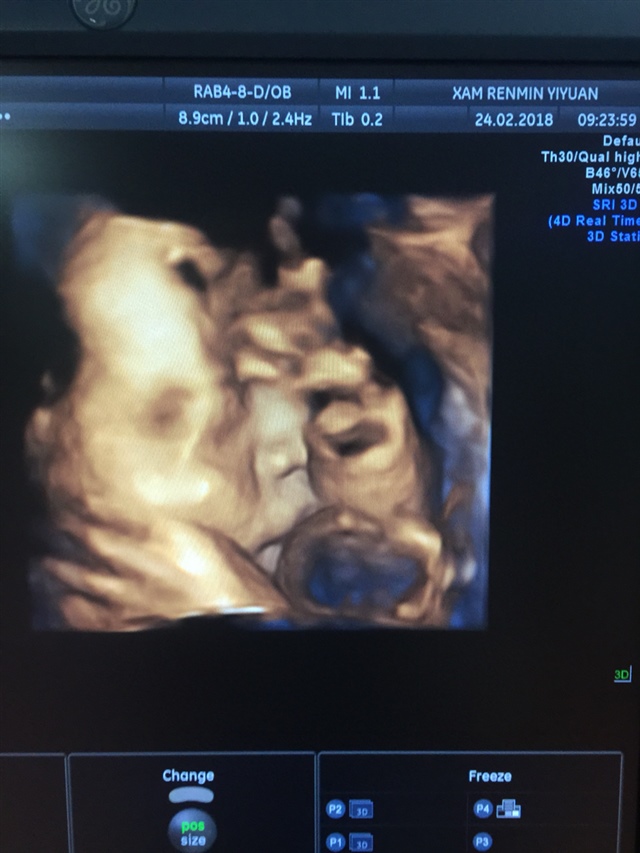

孕9周+3天

孕31周+3天